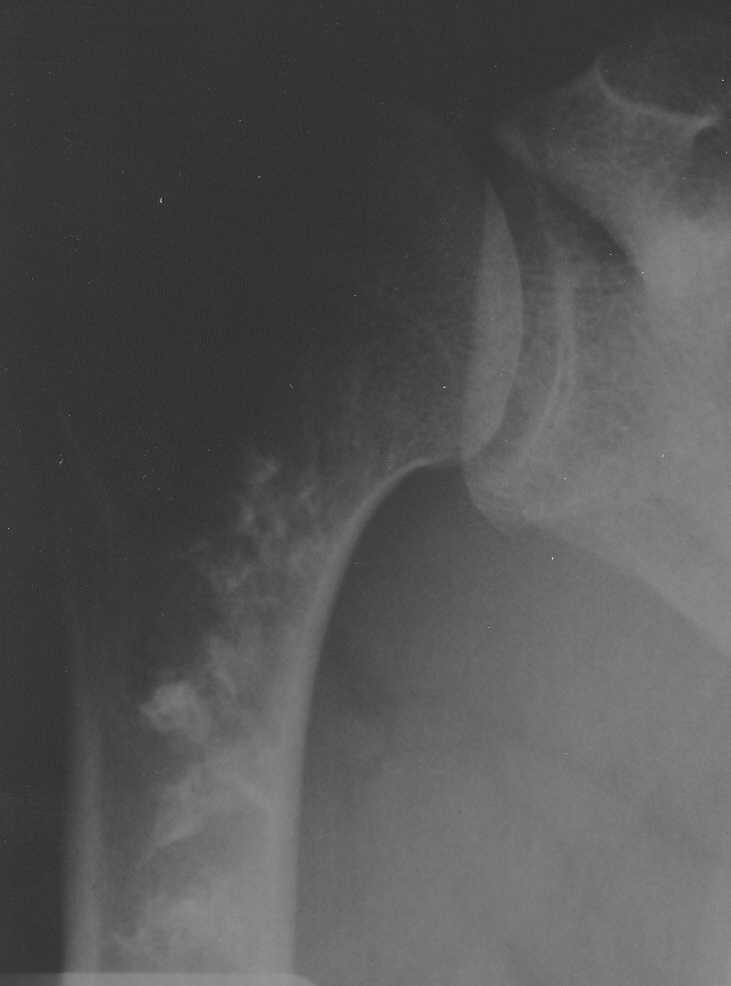

Обратился пациент с жалобами на боли в области плечевого сустава.

Боли беспокоят при движениях (поднятии руки, заведении руки за спину). В покое боли не

беспокоят. Кроме болей ни субъективно, ни клинически никаких данных. Получены вот такие

рентгенограммы:

Имя     : rentgen1.jpg

Размер  : 12529 байтов